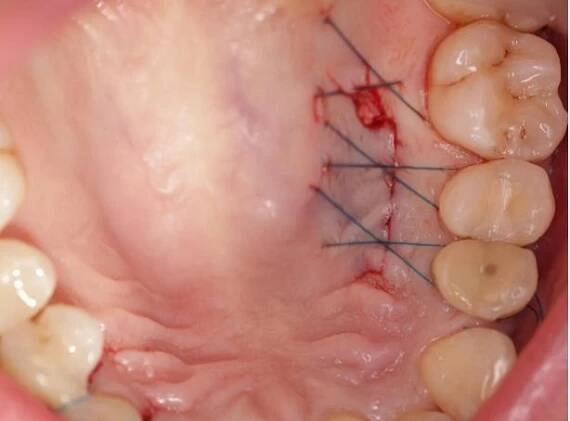

Překrytí odhalených krčků | M-DENT - Stomatologická ordinace v Hradci Králové